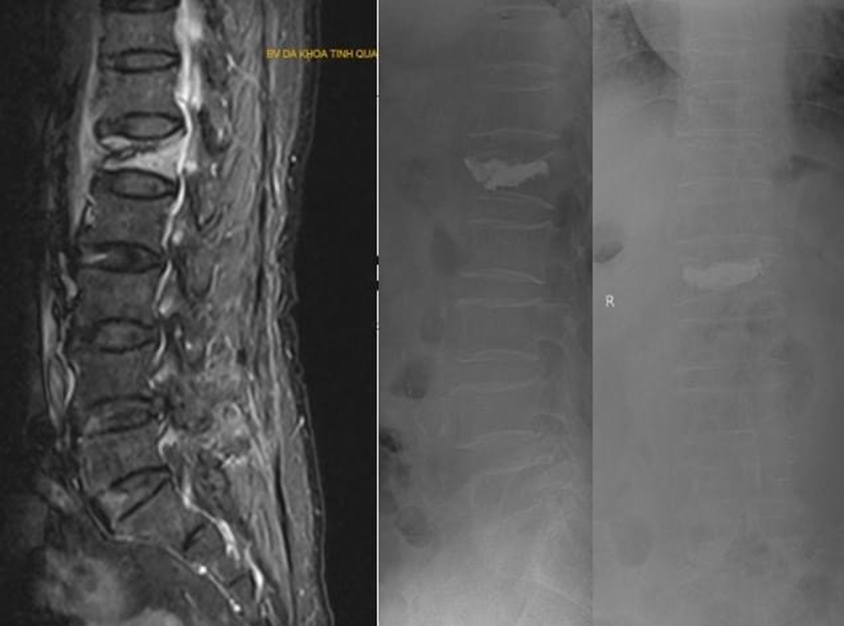

Hình ảnh bơm xi măng cột sống điều trị lún xẹp đốt sống